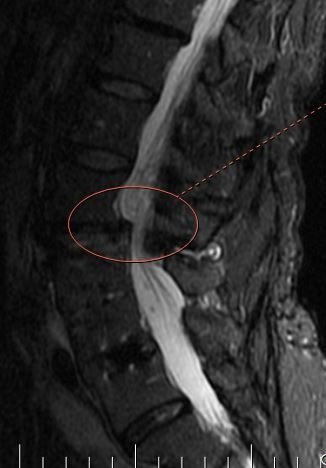

The MRI shows the side view of the low back [lumbar spine] showing the narrowing of the spine where the fluid seems to be cutting off in the middle of the lumbar spine [marked with an ellipse].